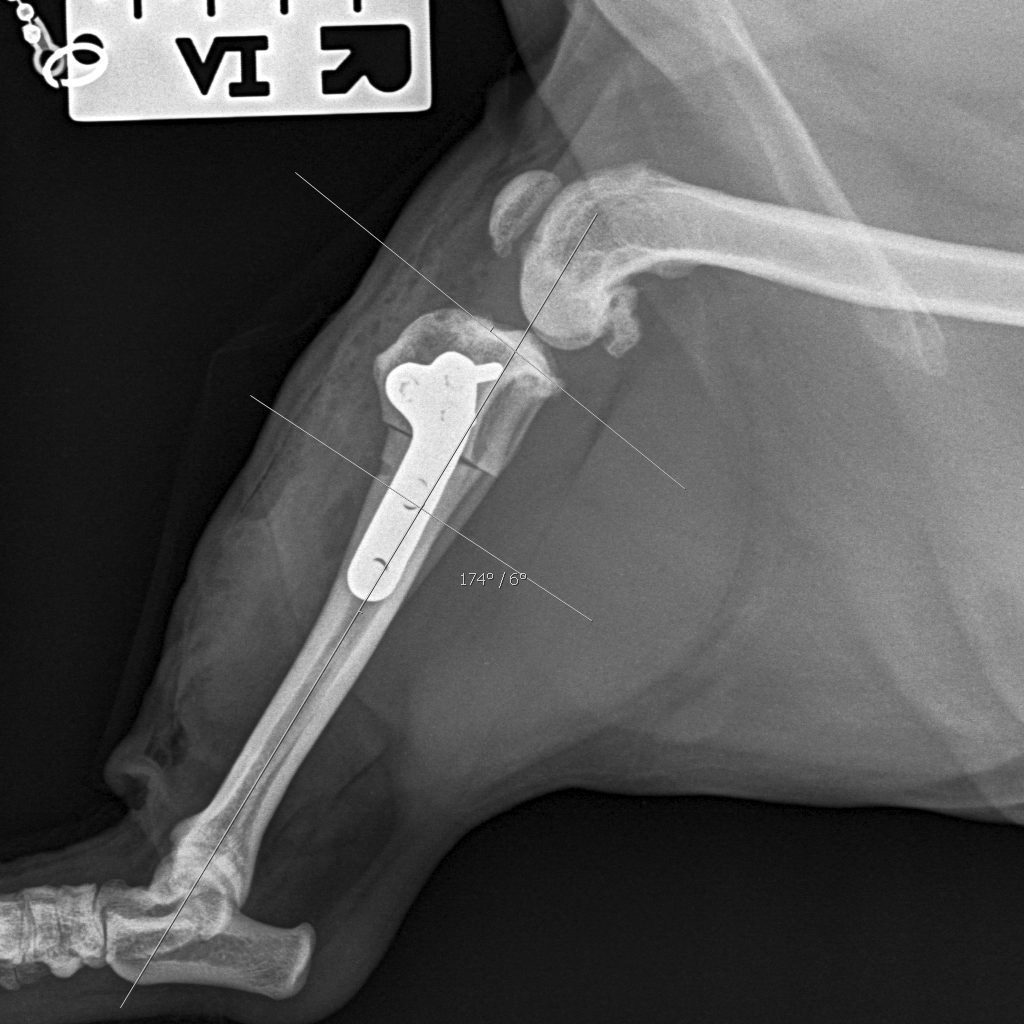

Fracture Repair

Many fractures can be managed by either internal (plate/ rod) fixation or external fixation (ESF). An estimate can be provided after review of radiographs, please include a size calibrated marker on films.